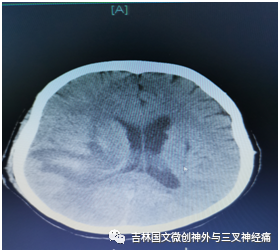

患者郝某,是一名糖尿病患者,既往有兩次腦出血病史,本次因突發(fā)意識(shí)不清于2020年11月12日急診來我院救治,經(jīng)檢查為:右側(cè)大量腦出血破入腦室,入院時(shí)患者已處于昏迷狀態(tài),呼吸、咳痰費(fèi)力,左側(cè)巴花斯基征陽性??紤]病人為第三次腦出血,可能存在血管畸形等血管病變情況,入院后立即安排頭部CTA檢查,結(jié)果回報(bào)未見明顯動(dòng)脈瘤及血管畸形等情況,考慮為高血壓、動(dòng)脈硬化引起腦出血,為了減少副損傷,經(jīng)與家屬溝通,我們采取了血腫腔置管液化引流手術(shù)治療。

術(shù)后引流良好,意識(shí)逐漸轉(zhuǎn)清,根據(jù)復(fù)查頭部CT結(jié)果拔出血腫腔引流,因腦室內(nèi)仍有大量血液,防止腦積水的發(fā)生,術(shù)后又采取了腰大池引流治療,徹底把腦室內(nèi)積血引流干凈;病人盡管意識(shí)恢復(fù),但咳痰能力差,為了保障呼吸道通暢,給予氣管切開促進(jìn)排痰,病情逐漸好轉(zhuǎn)。